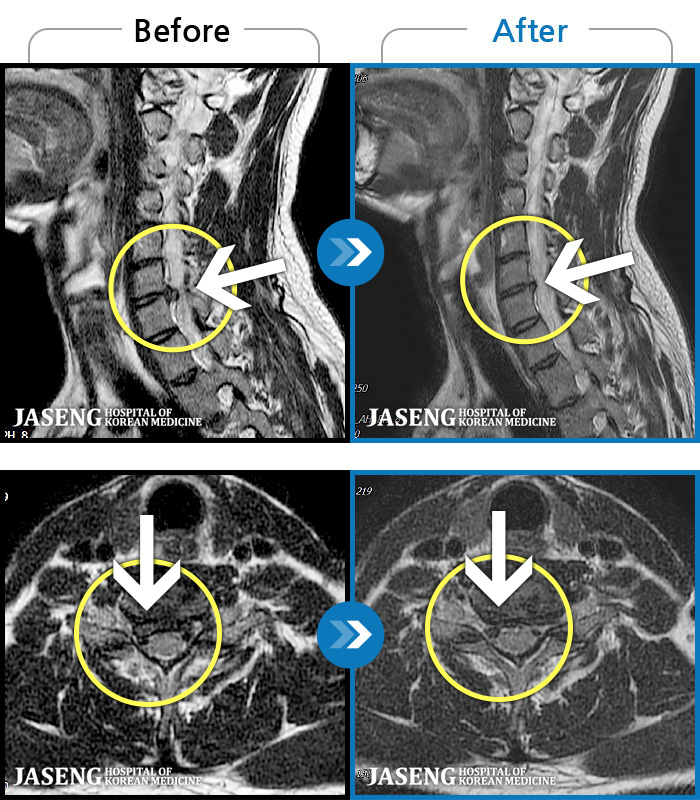

- MRI ġ

MRI ġ

56 MRI ũ ʸ Ȯϼ.